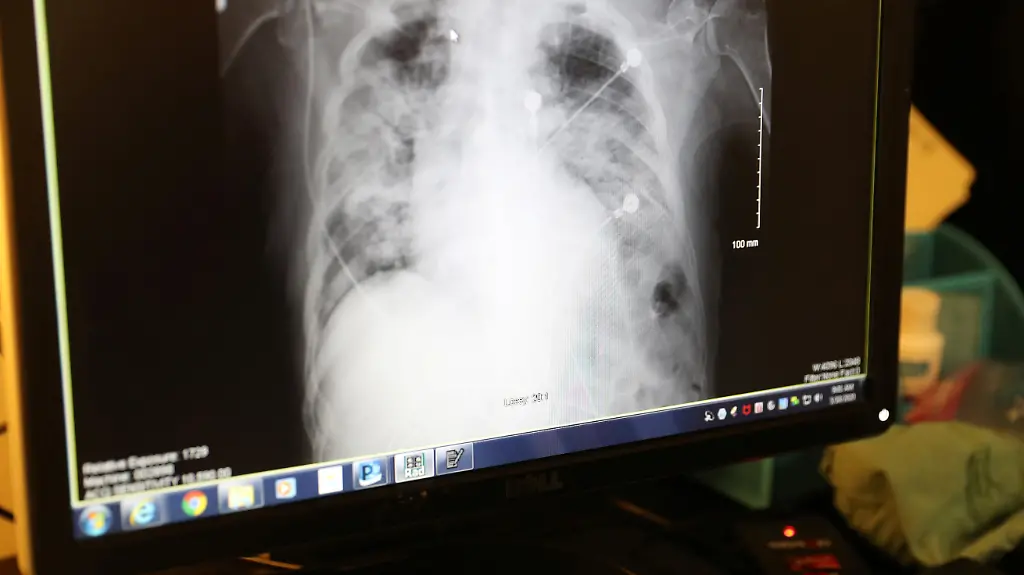

Ist die Lungenfunktion von Covid-19-Patienten so stark eingeschränkt, dass eine solche Versorgung mit Sauerstoff bei zunehmender Atemnot nicht mehr ausreicht, werden sie auf die Intensivstation verlegt und bekommen, in ein künstliches Koma versetzt, eine Beatmung über einen Schlauch in der Luftröhre. Eine solche Intubation birgt Risiken. So ist das Aufheben der Beatmung ein schwieriger Prozess - je länger sie dauerte, desto stärker sind neben anderen auch die zum Atmen benötigten Muskeln abgebaut. Gerade bei Älteren ist es schwierig, sie wieder bis zum Zustand zuvor aufzubauen. Auch reagiert die Lunge empfindlich auf Überdruck und auch auf den Sauerstoff, der der Beatmungsluft zugesetzt wird. Lungengewebe kann irreparabel geschädigt werden. Auch in anderen Organen kann eine künstliche Beatmung zu Schäden führen.

Über die Schläuche kann zudem zusätzlich zur Viruserkrankung eine bakterielle Infektion in der Lunge entstehen. Bei fast allen Covid-19-Patienten am Kölner Universitätsklinikum sei eine solche zweite oder gar dritte von Bakterien ausgelöste Lungenentzündung festzustellen, berichtet Kochanek. Über Langzeitfolgen etwa solcher Lungenentzündungen lassen sich Experten zufolge noch keine gesicherten Aussagen machen. Bei heftigeren Verläufen, etwa mit schwerem Lungenversagen und langer Beatmungsdauer, seien durchaus Restsymptome wie ein vermindertes Lungenvolumen zu erwarten, sagt der Mediziner Sven Gläser vom Vivantes-Klinikum Neukölln.